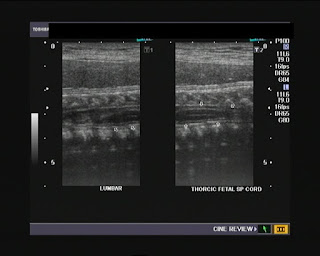

Fetal spinal cord (35 weeks gestational age):

Here are some still images showing the spinal cord of a fetus at 35 weeks gestational age:

I first captured this image showing the thoraco-lumbar region of the spinal cord with a convex 4 Mhz probe.

Then, I repeated the scan with a 9 Mhz probe. The tapered filum terminale and terminal part (conus medullaris) of the cord are seen in this ultrasound image (below): The spinal cord (arrows) is the hypoechoic tubular structure between those 2 echogenic (bright) membranes (the dura mater) within the spinal canal.